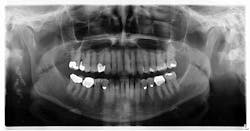

Patient: 77-year-old female

- Two corrugated, irregularly shaped radiopaque masses on the right posterior angle of the mandible

- Each lesion measures approximately 1 inch in length

- Area not tender to palpation

- Health history includes cholesterol and blood thinner medications, type 2 diabetes, history of COPD, high blood pressure, and sensitivity to penicillin